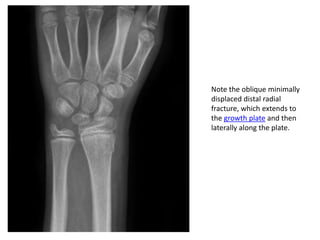

Note the oblique minimally

displaced distal radial

fracture, which extends to

the growth plate and then

laterally along the plate.

Note the obliqueminimally displaced distal radial fracture, which extends to the growth plate and then laterally along the plate.